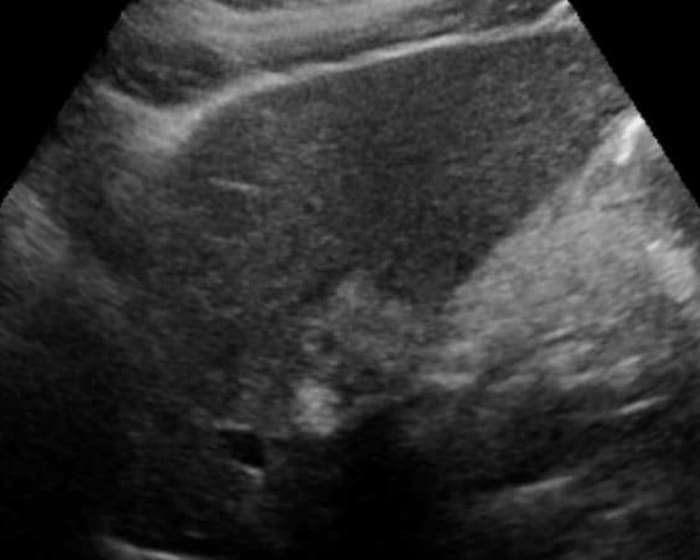

Ung thư đường mật

» Thông tin: Nữ giới – 56 tuổi.

» Lâm sàng: Viêm gan C.